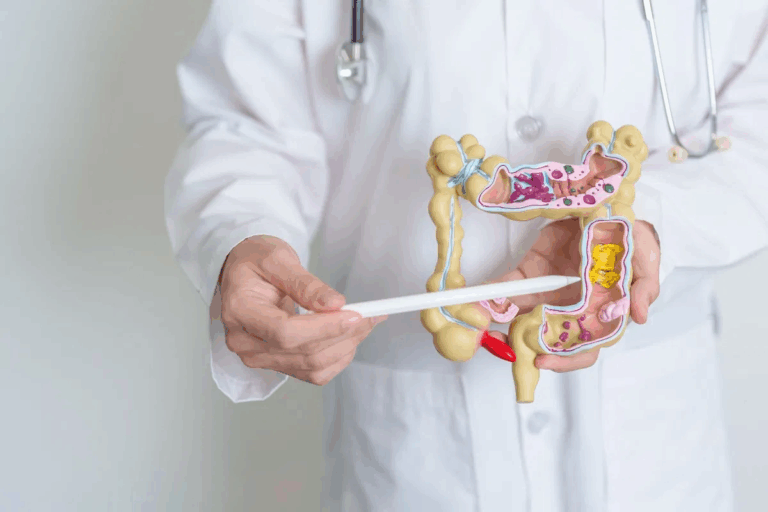

Kyphoplasty deals with the spine, so knowing spinal anatomy is important. The spine has parts like the cervical, thoracic, lumbar, sacrum, and coccyx. Kyphoplasty mainly focuses on the thoracic and lumbar areas.

- Vertebral body: The main weight-bearing part of a vertebra.

- Vertebral compression fracture (VCF): When a vertebra collapses.

- Pedicles: Bony parts that link the vertebral body to the back parts.

T12 and L1 are specific vertebrae in the spine. T12 is the twelfth thoracic vertebra, and L1 is the first lumbar vertebra. These are common sites for fractures, making them key for kyphoplasty.

Knowing which vertebrae are involved helps understand the procedure’s focus and results.